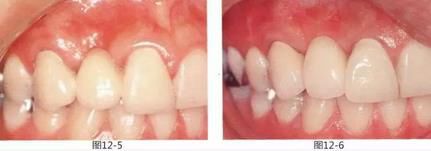

圖12-5  初診時。

圖12-6  佩戴最終修復體后。